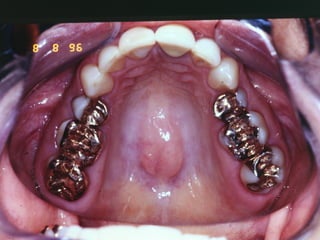

Tatuagem por Amalgama

• Impregnação

• Áreas de Abrasão na Mucosa

• Fragmentos em Área de Extração

• Uso de Fio Dental em Restauração Recente

• Retro-obturação Endodontica

• Pressão das Brocas das Turbinas de Alta

Rotação

• Aspectos Clínicos Radiográficos